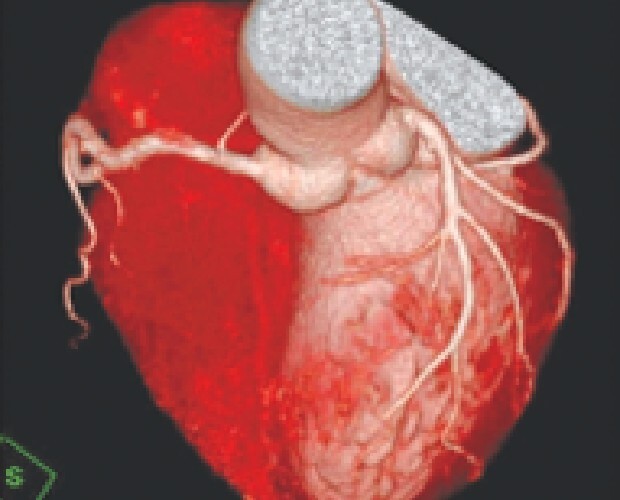

マルチスライスCTスキャナは寝台に横になるだけで頭部・胸部・腹部など体内を断層(輪切り)で撮影できる検査です。

従来装置(64列)に比べて高速、高精度の撮影が可能なだけでなく、患者様の体型に合わせて線量を可変できるため適切なX線量で検査できます。

診断や治療のために骨や血管の3D(立体的な三次元画像)を作成することもできます。